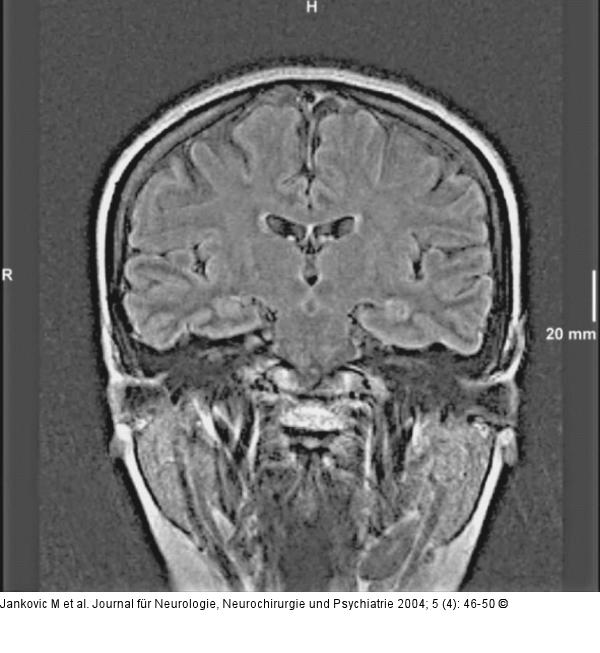

Abbildung 2: Epileptische Anfälle - intrathekale Fluoreszeinapplikation Die liquorsignalunterdrückte TIRM-Sequenz des Gehirns zeigt ein unauffälliges Signalverhalten der Hippokampusregion beidseits. |

Die liquorsignalunterdrückte TIRM-Sequenz des Gehirns zeigt ein unauffälliges Signalverhalten der Hippokampusregion beidseits. |